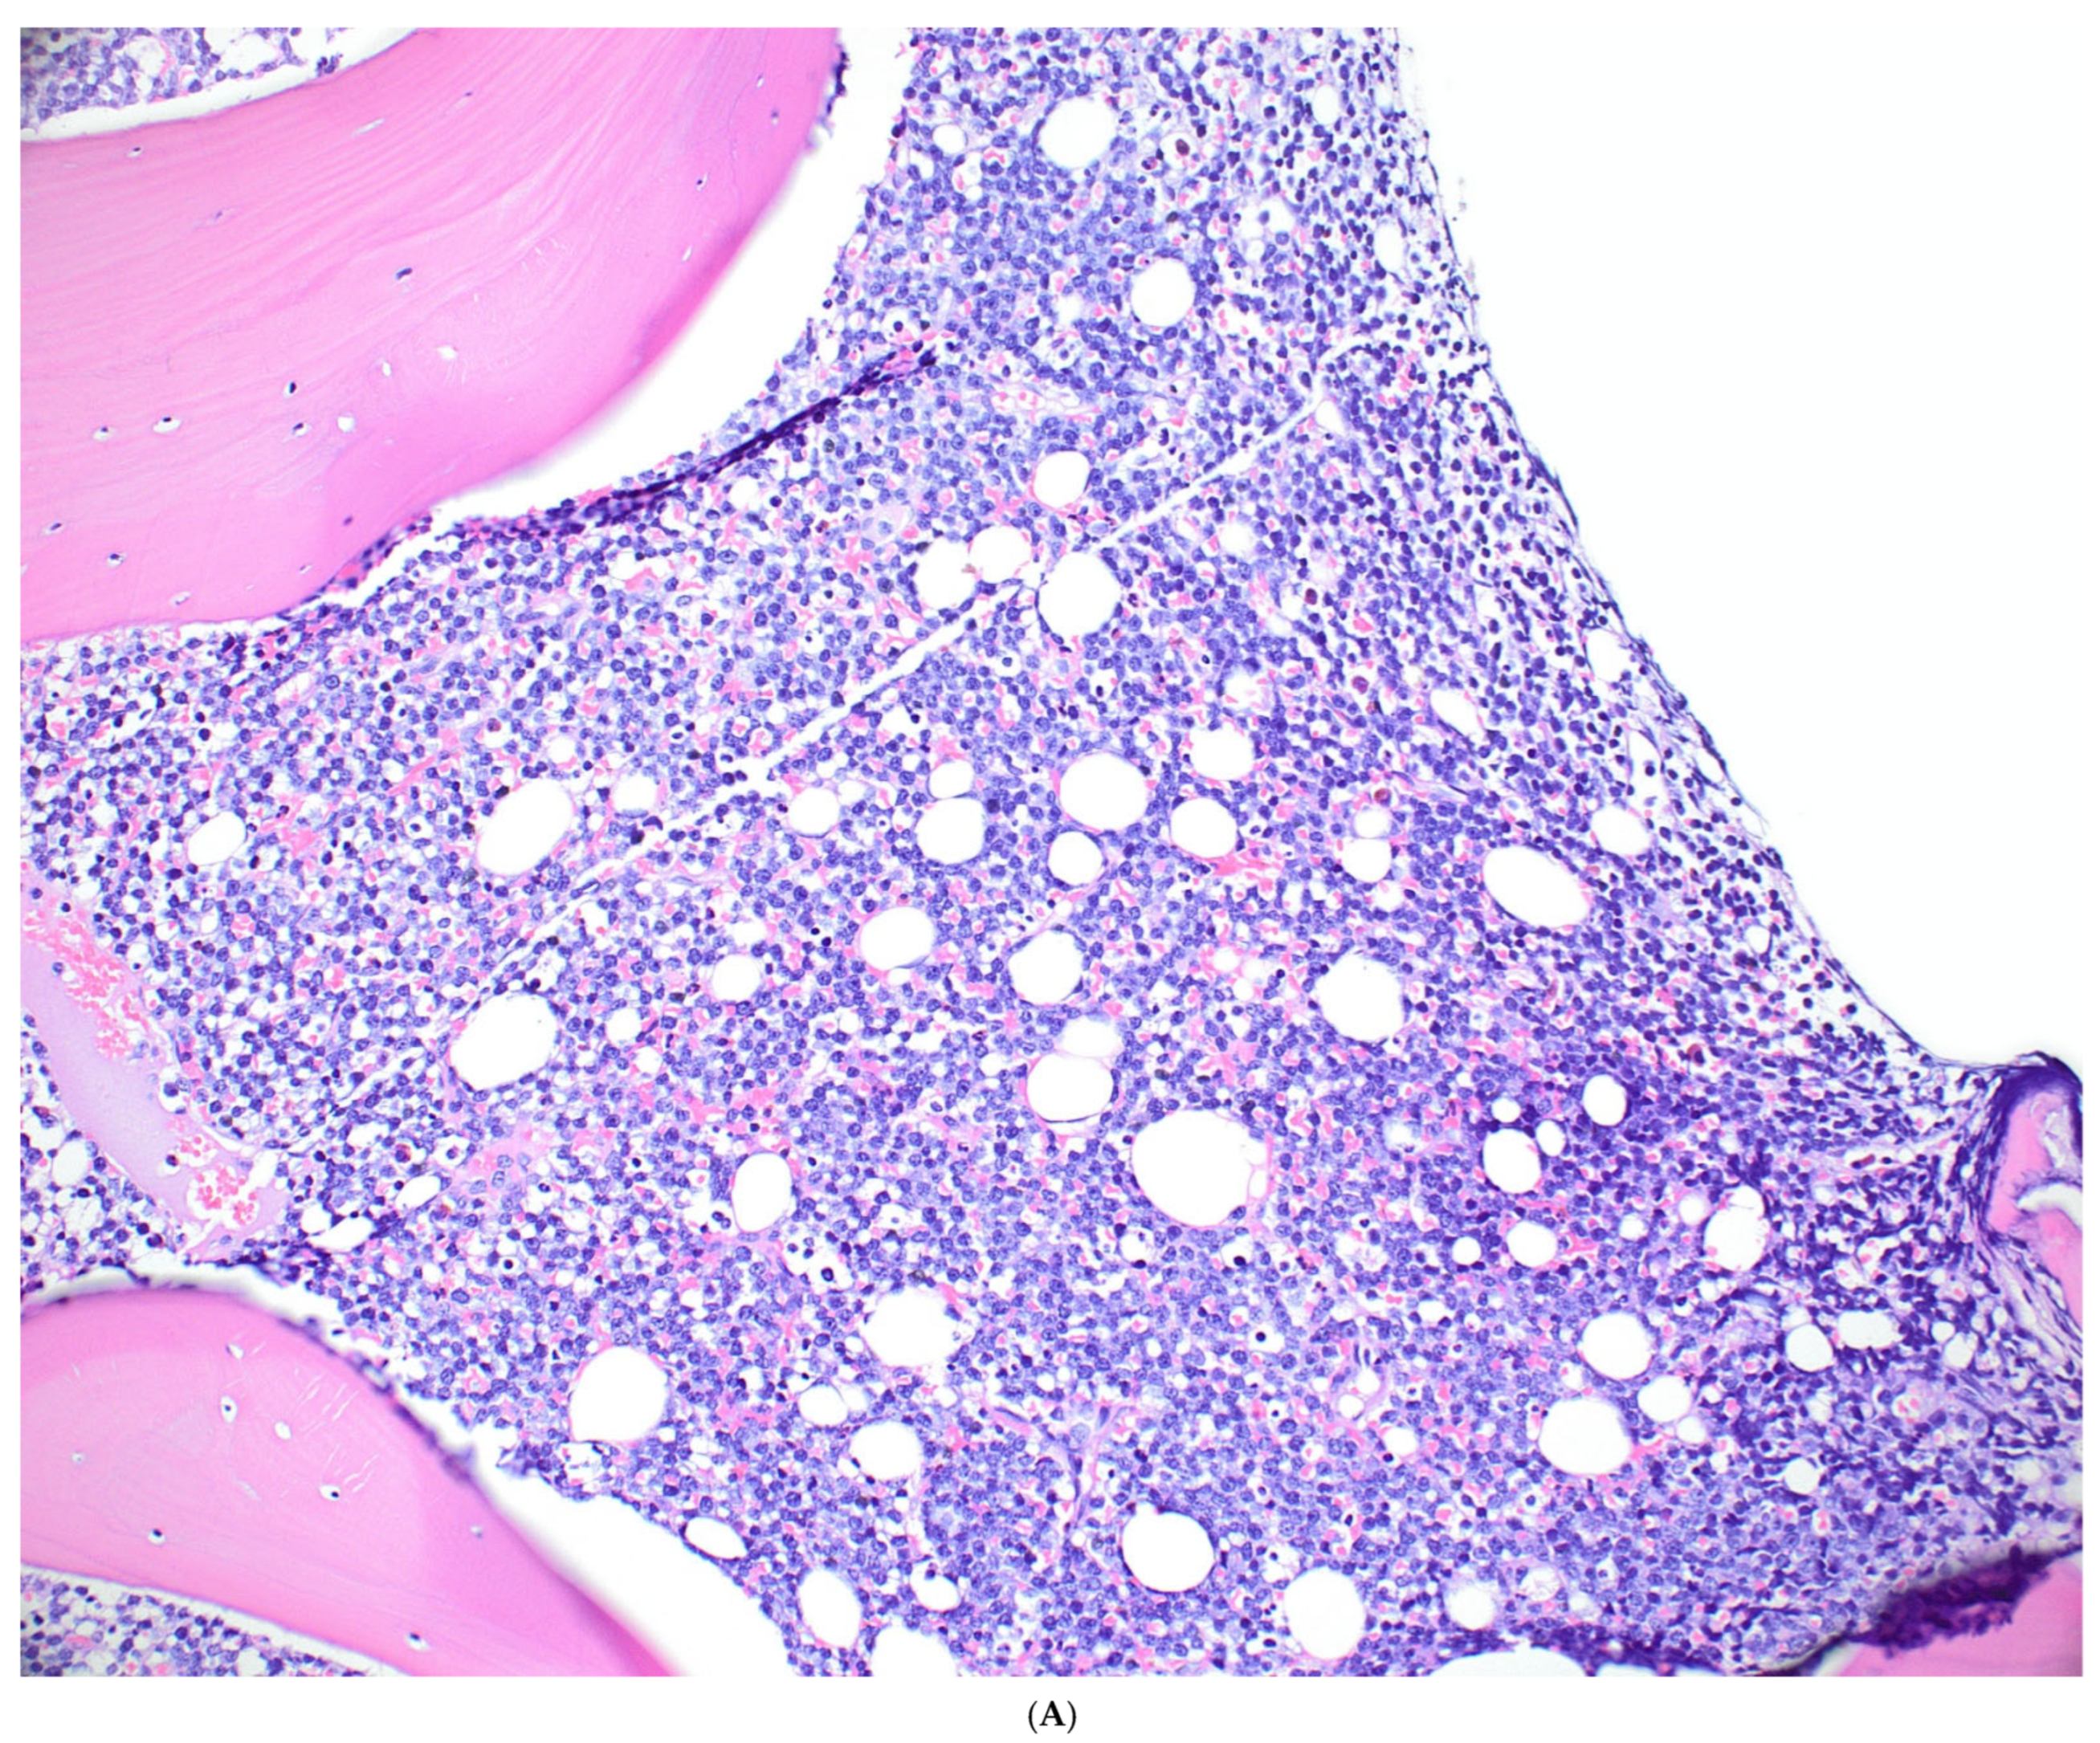

- Medium-sized, monomorphic lymphoma cells with basophilic cytoplasm and multiple small nucleoli

- Starry sky pattern, cohesive growth pattern